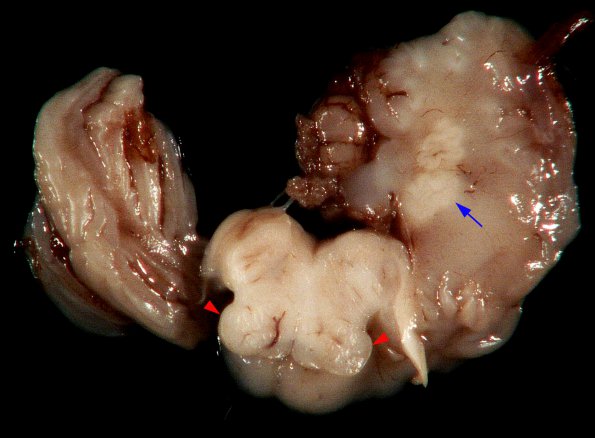

Washington University Experience | DEVELOPMENTAL MALFORMATIONS | Malformation - Inferior Olivary Nucleus (not CTT) | 1A Malformation, ION (Case 1) N8 ION and dentate dysplasia

Case 1 - Thirty two week gestation neonate with cerebellar dysplasia also involving dentate nucleus. --- Gross specimen shows unusual shape of ION (red arrowheads) and dysplastic dentate (blue arrow)